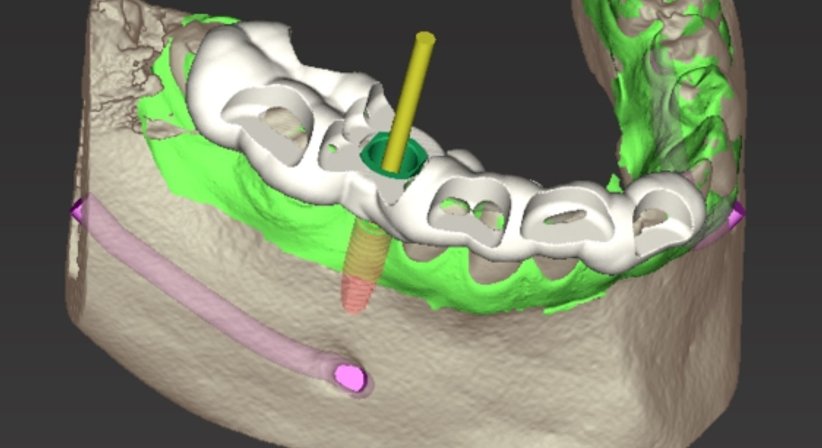

Ich führe die Implantation navigiert bzw. schablonengeführt durcht. Dreidimensionale Röntgendaten (DVT) und eine moderne 3D Planungssoftware mit entsprechendem Übertragungssystem ermöglichen eine exakt vorhersehbare und präzise Setzung des Implantates. Zudem ermöglicht die Software eine genaue Auswertung der vorhandenen Knochensubstanz.

Das Einbringen des Zahnimplantates kann also schon vor Implantatsetzung am Computer in Form eines dreidimensionalen Patientenmodells simuliert werden.

Danach wird die virtuell geplante Implantatposition mithilfe einer computergefertigten, in 3D Druck hergestellten Führungsschablone (Bohrschablone) an die gewünschte Stelle im Kieferknochen übertragen, wodurch das Implantat optimal platziert werden kann.